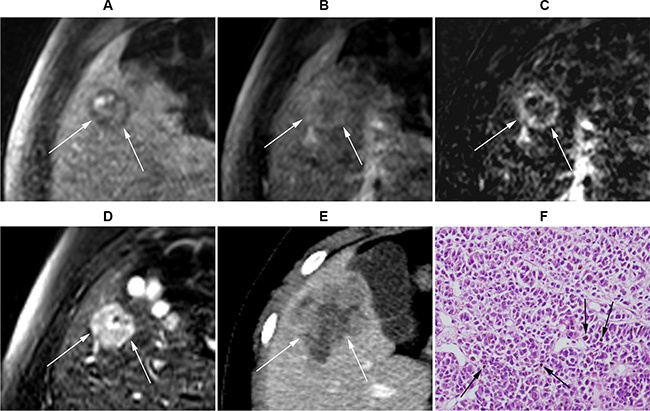

Figure 4: Gadoxetic acid-enhanced MRI of a 21-year-old male with uveal melanoma. (A) Precontrast T1-weighted MR image. (B) Post-contrast-enhanced portal venous phase T1-weighted image. (C) Subtraction image (portal venous phase – precontrastT1-weighted image). (D) T2-weighted image. A 2.2 cm (arrows) metastasis lesion at segment 5 is observed, which was graded to show positive enhancement and intermediate high T2 SI. (E) CT image at the same level obtained 2 months later demonstrated that the lesion size increased to 4.7 cm. (F) Histopathological exam (H&E stain ×200) of liver biopsy obtained from the S5 lesion revealed malignant cancer cells with melanin pigments (arrows), consistent with malignant melanoma.